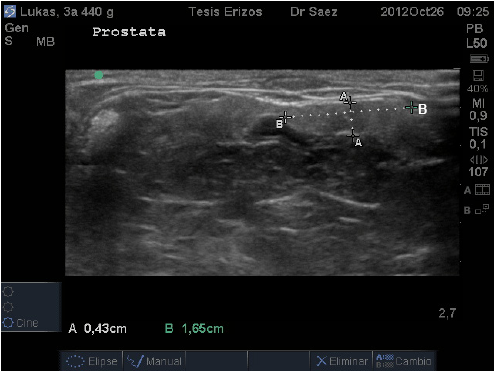

La próstata se localizó caudal a la vejiga, en un corte transverso fue posible visualizarla ventral al colon descendente y medial a cada testículo. En este corte, en cuatro individuos, cada lóbulo presentó una forma de “gota” con su eje mayor horizontal, siendo más redondeada lateralmente y fusiforme hacia medial (FIG. 8).

En el resto de los pacientes, se observó cada lóbulo de forma aplanada y alargada, teniendo la misma altura tanto medial como lateralmente, o si presentaban el extremo medial aguzado, éste era muy sutil (FIG. 9).

En el corte longitudinal presentó la misma forma, es decir, aquellos individuos que presentaron lóbulos prostáticos en forma de gota al corte transverso, la mantenían al corte longitudinal, siendo el extremo craneal el más redondeado y el extremo caudal más aguzado. Y aquellos individuos que presentaron forma aplanada al corte transverso, la mantenían al corte longitudinal. El órgano se observó con ecogenicidad media, de granulado fino y homogéneo.

En relación a la Próstata, llama la atención la diferencia de valores obtenidos para tamaño prostático entre individuos, llegando en algunos casos a bordear 1 cm, pudiéndose suponer una relación entre éstos valores y el peso del animal, sin embargo los resultados estadísticos de correlación demostraron relación baja entre las variables y no significativa (P˃0,05). Se puede inferir, por lo tanto, que el tamaño de la glándula no es constante entre individuos sanos, independiente de otras variables como el peso, lo que se debe tener presente para no cometer errores diagnósticos al evaluar este órgano.